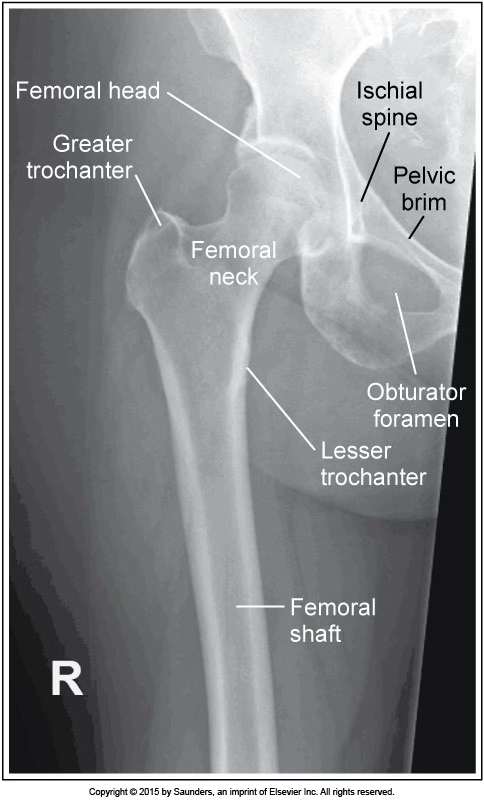

AP femur

accurate positioning